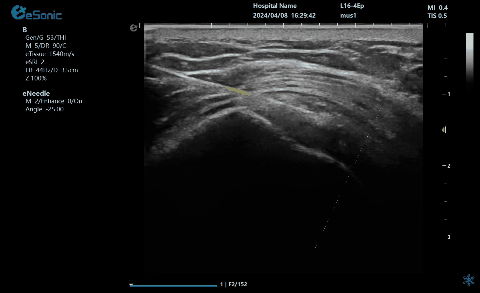

穿刺针智能MAP技术在钙化性肌腱炎的应用

【背景】:冈上肌腱内见强回声钙化灶(见标识箭头)

【治疗】:穿刺捣碎钙化灶,并抽吸;注射药物,消炎止痛。

【痛点】:普通穿刺增强,不能有效区分同为强回声的针尖和钙化灶,医生凭借经验穿刺到钙化灶。

【方案】:穿刺针智能MAP技术,采用智能彩色叠加,避免针与钙化灶混叠而难以区分,帮助引导针尖  精准到达并抽吸钙化灶。